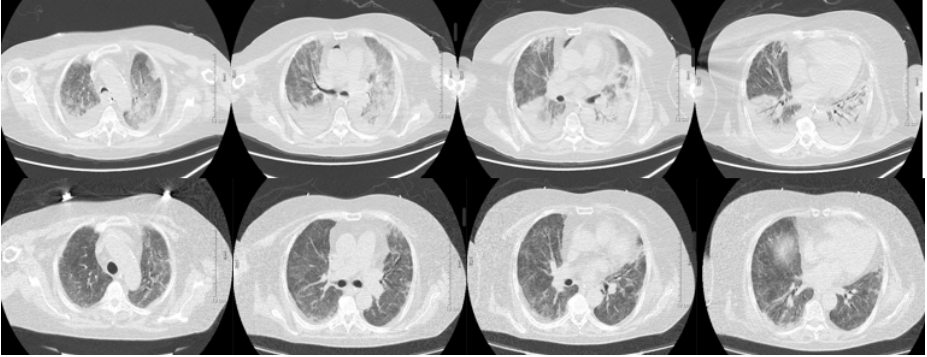

对于ARDS的治疗,目前证据级别较高的治疗手段主要是支持治疗。但对因治疗才是改善预后的根本。同时,一些疾病虽然影像学表现和病程变化符合ARDS的标准,但有特异性的病因。如果不能及时查明病因,会延误治疗时机。图1所示,胸片可见双肺多发渗出影,胸部CT可见以右肺为主的大片磨玻璃渗出,小叶间隔增厚。该患者病情迅速进展,胸片出现双肺弥漫渗出影。虽然病程及影像变化符合ARDS的特点。但经过外科肺活检和肺泡灌洗后,BALF细胞学可以发现吞噬大量磷脂蛋白的巨噬细胞, PAS染色阳性。同时,病理提示肺泡腔及小气道中大量PAS染色阳性的物质。该患者通过活检和细胞学诊断为肺泡蛋白沉积症(PAP)。图2胸片可见两侧弥漫渗出,BALF低倍镜下可见大量嗜酸细胞浸润,最终诊断为急性嗜酸细胞性肺炎。由此可见,ARDS的病因诊断极为重要。

图1  一例PAP患者影像及病理表现